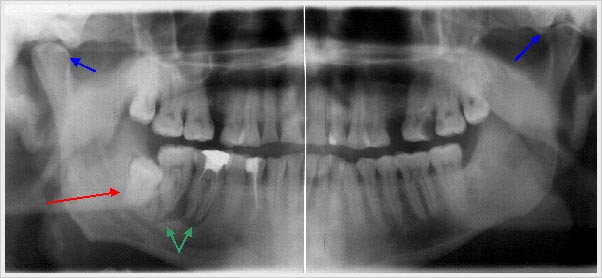

Eine Röntgenaufnahme des gesamten Kiefers (Panoramaschichtaufnahme) zum Ausschluss zahnärztlicher und kieferchirurgischer Krankheitsursachen. (z.B. verlagerte Zähne, chronische Entzündungen von Zahnwurzeln, versteckte Karies (besonders „hidden caries“) oder parodontitis-bedingtem Knochenabbau) ist zwingend.

Panorama-Aufnahme mit einem verlagerten Zahn (Zahn 48 = rechter unterer Weisheitszahn) -roter Pfeil-einer chronischen apicalen Parodontitis der Zähne 46 und 47 -grüne Pfeile-

und außerdem Hinweise auf Unterschiede in den Kiefer-

gelenken -blaue Pfeile-